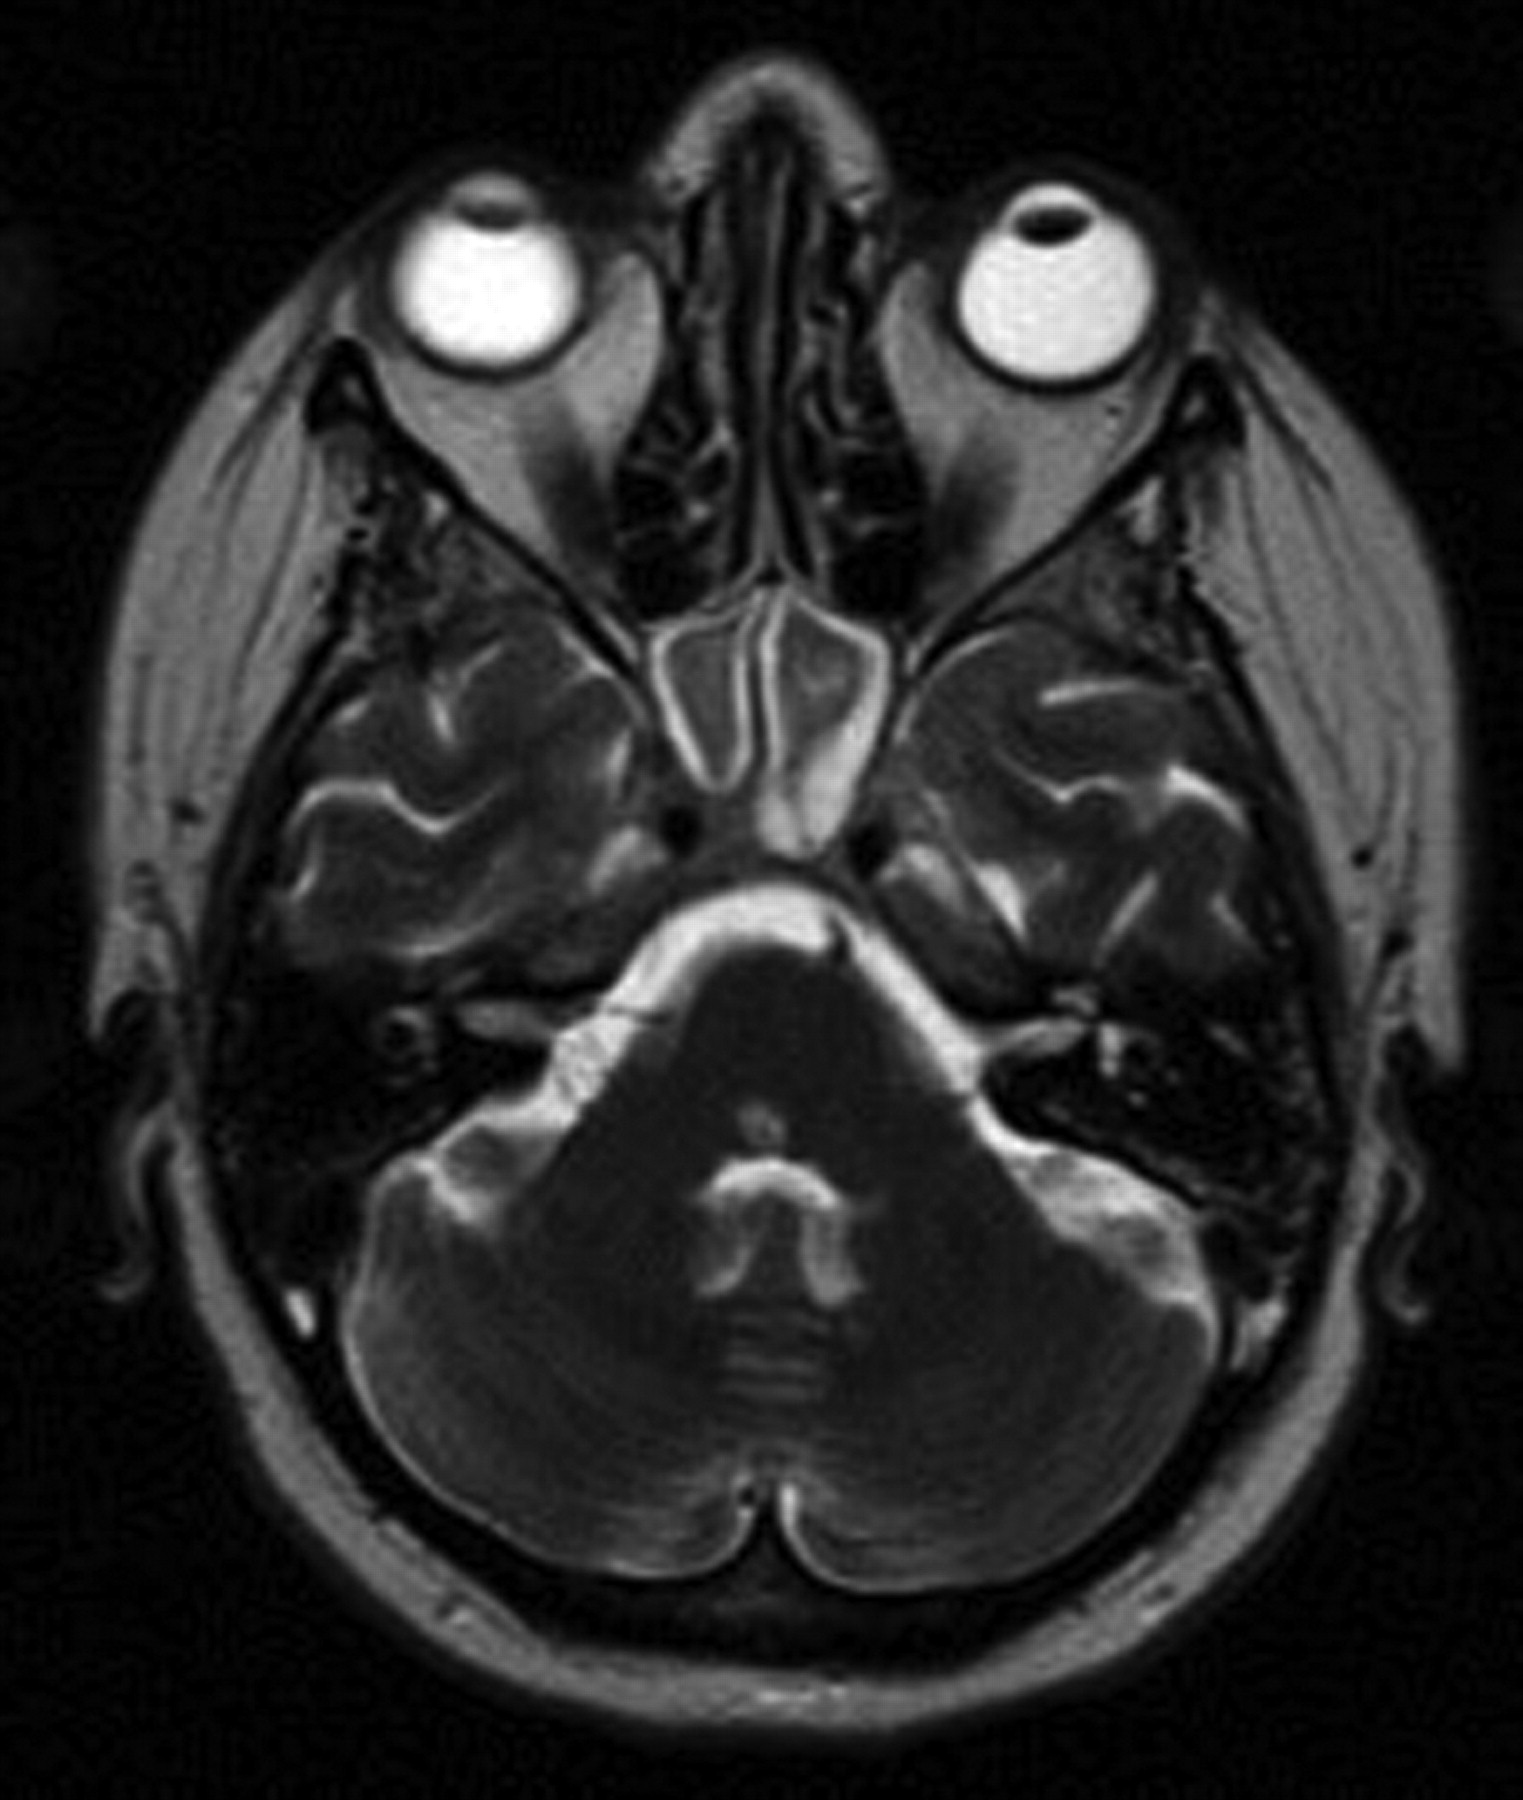

One hour after the procedure, the patient began to complain of “jumping” vision and unsteadiness associated with nausea and vomiting. On examination, she had a right internuclear ophthalmoplegia, mild right-sided facial weakness involving the lower motor neuron, drift of the left upper extremity, and diminished sensation in the left distal arm. An urgent MR imaging demonstrated T2-weighted abnormality in the pons and upper medulla and a diffusion-weighted imaging (DWI) abnormality within the dorsal pons (Fig 2) that was much smaller than the region of T2 change. The MR angiogram and MR venogram were notable for a dominant right transverse sinus and a patent basilar artery. These imaging findings were concerning for a brain stem infarction. She was admitted to the neurosurgical intensive care unit for aggressive fluid hydration and was given 10 mg of dexamethasone (Decadron) every 6 hours and 325 mg of aspirin daily.

A–C. Initial MR imaging after a change in the patient's neurologic examination. A, Axial T2-weighted MR imaging demonstrating diffuse edema within the pons. B, Sagittal T2-weighted MR imaging demonstrating the cranial-caudal extent of edema at the pontomedullary junction. C, Axial DWI MR imaging showing a region of restricted diffusion, highly suggestive of infarct, within the dorsal pons.

Overnight, she deteriorated further with complaints of severe diplopia bilaterally on lateral gaze. On examination, she had complete paralysis of horizontal gaze as well as increased right facial and left upper extremity weakness. She also reported some difficulty swallowing, and a formal swallowing evaluation confirmed moderate dysphagia. For the next 48 hours, she developed new weakness involving the left leg, and she had decreasing oxygen saturations and increasing stridor, requiring intubation and an eventual tracheostomy. Repeat MR imaging demonstrated diminished T2-weighted abnormality within the pons and evidence of hemorrhagic conversion on gradient-echo sequences. Another MR imaging examination performed 3 weeks later revealed diminished T2-weighted abnormality within the pons and medulla but continued DWI abnormality within the dorsal pons, extending in a linear wedge to the right ventral pontine surface. She was transferred to acute rehabilitation after 3 weeks on the neurosurgical service, at which time her hemiparesis and facial weakness were improving and the sensory deficits had resolved.

Follow-Up

Repeat MR imaging 3 months after IPSS demonstrated very scant T2-weighted abnormality, except in the region coinciding with the fixed DWI abnormality in the dorsal pons (Fig 3). At 6-month follow-up, she reported diminished diplopia but had persistent bilateral lateral gaze palsy. She did, however, have complete resolution of her right facial weakness and left-sided hemiparesis. In addition, her tracheostomy had been reversed and her swallowing was substantially improved.

MR imaging at 3 months after IPSS. Axial T2-weighted MR imaging demonstrating near-complete resolution of edema within the brain stem but a region of hyperintensity within the dorsal pons corresponding to the region of infarction.

In our 5½-year experience, 44 patients underwent IPSS after either an equivocal work-up or after previous failed surgery. The initial 35 consecutive patients sustained no complications as a result of the procedure, and the 8 most recent procedures have also been free of complications. However, 1 of 44 patients did sustain a partially reversible brain stem injury. After reviewing the literature, we believe that the prominent anterior pontomesencephalic veins seen in our patient during the right IPS venogram was an example of a variant pattern of venous drainage surrounding the brain stem and contributed to her injury. Whether this was from the catheter occluding venous outflow or from focal venous hypertension as a result of contrast injection remains unclear. There is some evidence of contrast reflux superiorly into the cranial aspect of the anterior mesencephalic vein instead of only inferior venous drainage (Fig 1B). This raises the possibility of some degree of outflow obstruction or slowing. During the procedure, the patient reported no symptoms, and there were no changes in the patient's examination or vital signs that would have caused us to terminate the test. The resulting injury on the first MR showed diffuse brain stem edema with a smaller region of actual infarction. The region of injury seen on T2-weighted sequences is consistent with our patient's neurologic examination with involvement of the fibers of pontomedullary cranial nerves (VI, VII, IX, and X), the paramedian pontine reticular formation, medial longitudinal fasciculus, portions of the corticospinal tract, medial lemniscus, and spinothalamic tracts. As the edema in the brain stem resolved, best seen on the evolution of T2-weighted sequences on serial MR imaging, the patient's sensory, motor, and lower cranial nerve deficits also resolved. The resulting infarct on the 3-month follow-up MR imaging confirmed a persistent abnormality on T2-weighted sequences within the dorsal pons that extends ventrally (Fig 3). The patient's neurologic examination after 6 months suggests that with the resolution of brain stem edema, only the fibers of the sixth cranial nerve, medial longitudinal fasciculus, and paramedian pontine reticular formation remain damaged. On the basis of the MR imaging findings, this is not surprising.